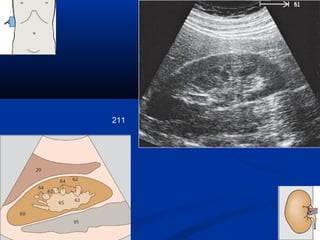

211